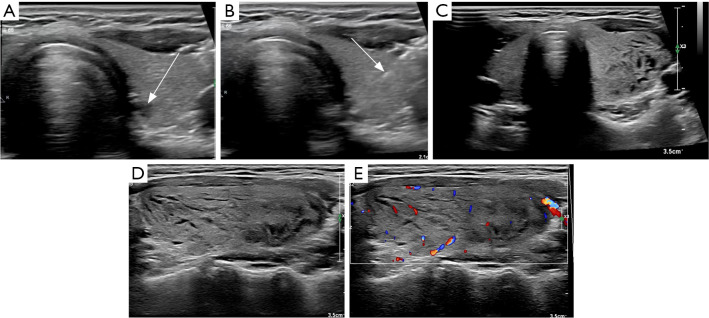

Results: ATTS following FNA is a rare complication. Among the 28 total cases (10 institutional, 18 literature), 89% were female. Bilateral goiter occurred in 71%. Symptoms typically emerged within one hour following FNA, resolving spontaneously within 24 hours in 79% of cases. Neck pain/swelling (54%) was common; severe complications (dyspnea, cardiac arrest) were rare (3%). Ultrasound revealed unilateral/bilateral goiter with linear/patchy hypoechoic areas and preserved vascularity. Non-pharmacological management sufficed for most patients.

Conclusions: ATTS following FNA is self-limiting, with distinct ultrasound findings. Clinicians should prioritize airway management in severe cases and avoid unnecessary interventions in mild presentations.